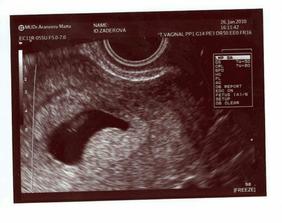

Však to znáte jak to začíná, řeknou si dva "máme se rádi" a už začínají snahy o miminko. Antikoncepci jsem vysadila někdy v září 09 a v prosinci začalo snažení Smiling...Věřtě nebo ne povedlo se nám to hnedle na poprvé, dělala jsem si asi tři testy, které nevyšly pozitivně, avšak 4.1.2010 se na testík objevily dvě //, no nemohla jsem tomu uvěřit, ale byly tam! Hnedle jsem volala mé kamarádce a málem jsem jí vyděsila k smrti, páč jsem to podala velmi vážně, ale nakonec to skončilo jásotem Smiling...Mému manžílkovi, který už to tušil jsem to řekla 5.1.2010, koupila jsem dudlíček - růžový (moc si přeji holčičku) a zabalila ho jako opožděný vánoční dárek, reakce při vyslovení, že budeme mít miminko, byla nádhérná, se slzami v očích zvolal "já budu táta!"